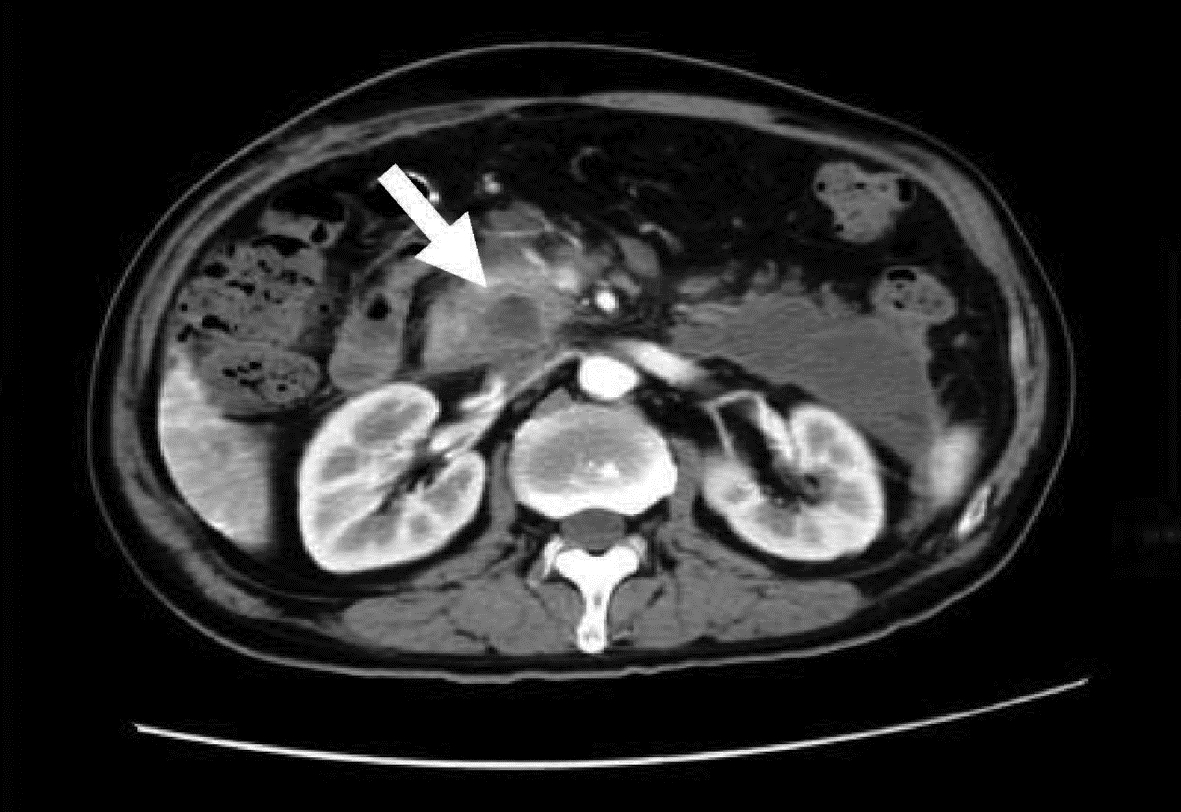

Efficacy of magnetic resonance IDEAL-IQ technique in diagnosis of fat and iron deposition in acute pancreatitis

Huifang FAN, Qiang CHEN, Xiaojun YUAN, Lin LUO

2022, 38(10): 2320-2324. DOI: 10.3969/j.issn.1001-5256.2022.10.022

Abstract(1240) HTML (498) PDF (2190KB)(69)

Abstract:

Objective  To perform quantitative evaluation of fat and iron deposition in the pancreas of patients with acute pancreatitis (AP) based on the IDEAL-IQ quantitative parameters fat fraction (FF) and relaxation rate (R2*), and to investigate the efficacy of this technique in the diagnosis of AP.  Methods  A total of 72 patients with AP who were diagnosed and treated in The First Affiliated Hospital of Baotou Medical College, Inner Mongolia University of Science and Technology from October 2020 to October 2021, were enrolled as case group, and 82 healthy controls who underwent physical examination during the same period of time were enrolled as control group. The abdominal IDEAL-IQ sequence test was performed for both groups using GE 3.0T magnetic resonance instrument, and FF and R2* values were measured on post-processing workstation. The t-test was used for comparison of normally distributed continuous data between groups, and the Mann-Whitney U test was used for comparison of non-normally distributed continuous data between groups. A receiver operating characteristic (ROC) curve analysis was performed for the parameters with statistical significance, and area under the ROC curve (AUC) was used to evaluate the diagnostic efficacy of parameters.  Results  Compared with the control group, the case group had significantly higher FF value (Z=-10.01, P < 0.001) and R2* value (Z=-3.73, P < 0.001), while there were no significant differences in FF and R2* values between mild AP and moderate-to-severe AP (P > 0.05). FF value had a sensitivity of 100% and a specificity of 90.2% in the diagnosis of AP, while R2* value had a sensitivity of 48.6% and a specificity of 86.6% in the diagnosis of AP.  Conclusion  The quantitative parameter FF value of magnetic resonance IDEAL-IQ technique has relatively high sensitivity and specificity in the diagnosis of AP, and it is a specific index for the diagnosis of AP and holds promise for clinical application.